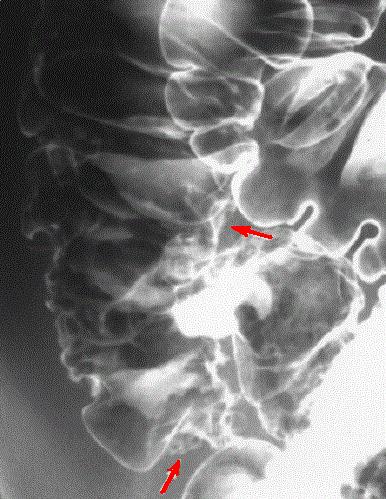

Au stade evolutive

image de ulceration marque en circumferentiel (

fleche rouge ) et deformation legere de la region

ileo caecale . Image radiologique en double de

contrast . . |